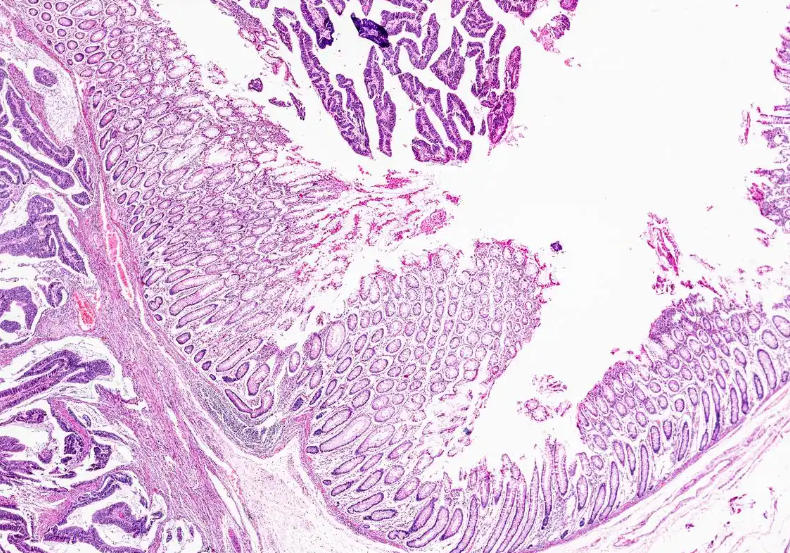

Animal slices provide clear views of the internal structure and cell morphology of organisms, which is crucial for understanding biological development and physiological processes. By observing slices at different developmental stages, students can understand the entire developmental process from fertilized egg to mature individual, as well as the formation and changes of various organs and systems. Furthermore, slices can help students observe structural changes in organisms under specific physiological conditions, such as stress responses and metabolic activities, thereby deepening their understanding of the physiological functions of organisms.